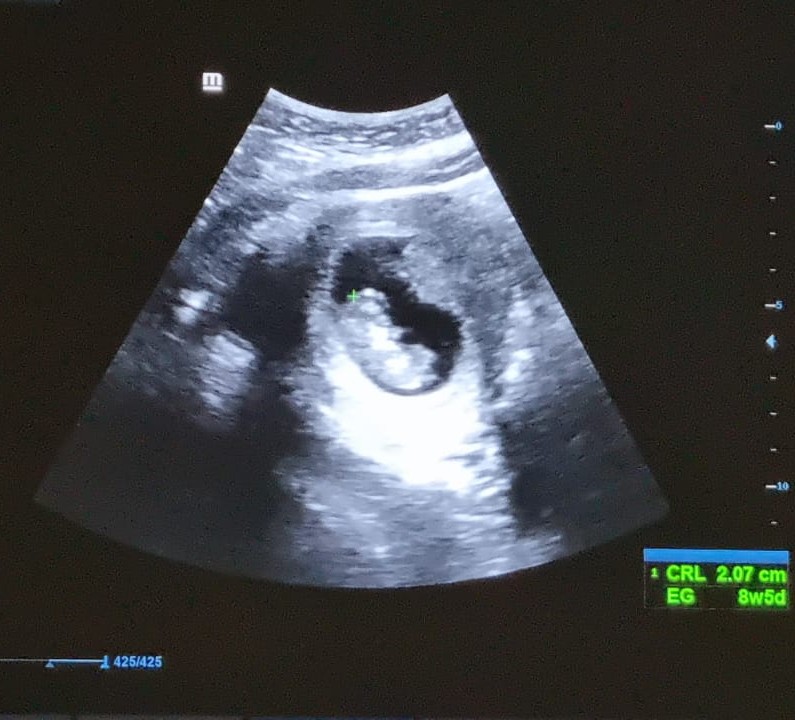

¡Nos comprometimos en Bacalar! 💍, y decidimos tener a nuestro hamburguesito

Nos enteramos que nuestro hamburguesito ya venía en camino.